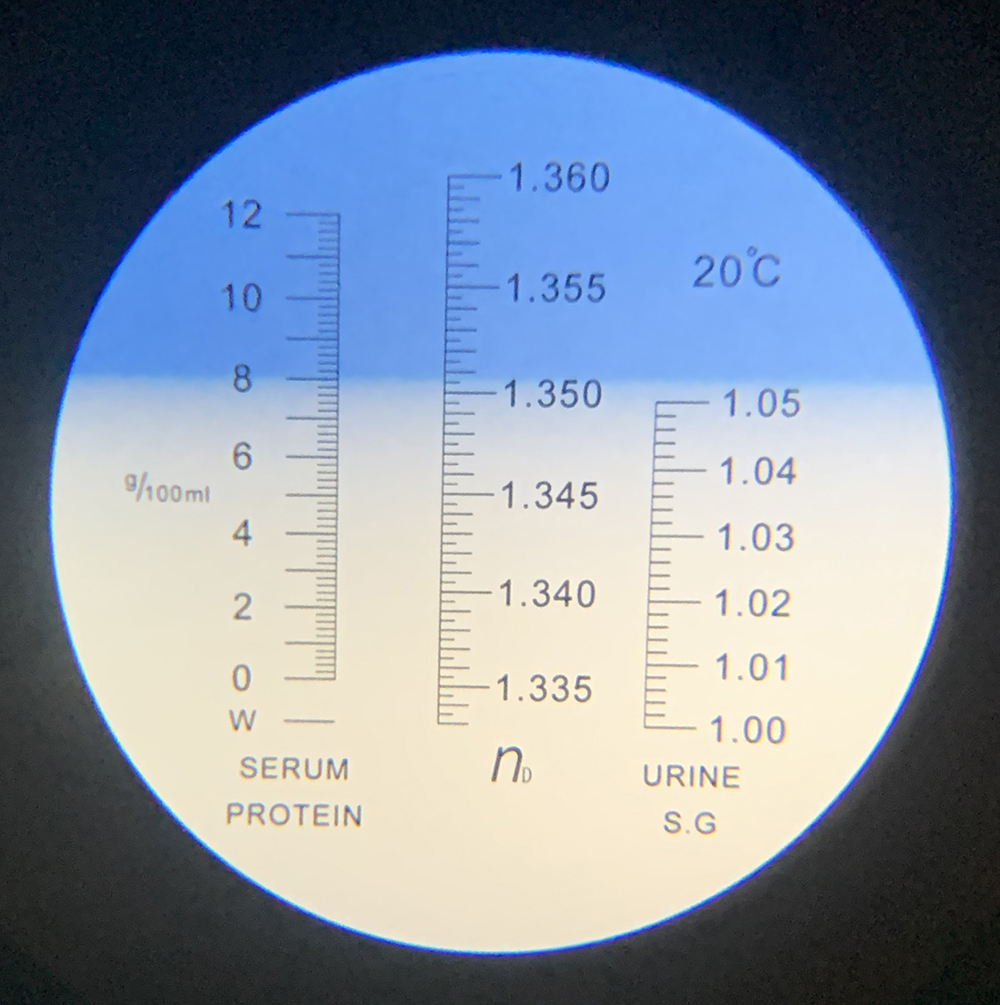

De urine die bij de balie wordt ingeleverd of na een nachtje bij ons verblijven is opgevangen, wordt in ons laboratorium nagekeken. Er wordt o.a. gekeken of er glucose of eiwit in de urine zit, of er bloed in aanwezig is, wat de zuurtegraad is en of er ontstekingscellen in aanwezig zijn.

Tevens wordt de concentratie van de urine bepaald. Als laatste wordt er onder de microscoop gekeken naar de hoeveelheden bloed- en ontstekingscellen, of er niercellen in zitten en of er eventueel kristallen in aanwezig zijn (blaasgruis).